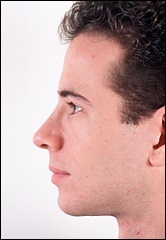

A fénykép a bal oldalon mutatja egy ember tipikus megnövekedett nazális gerinc. Ez jelentősen növeli az orrát előre. A fénykép után a művelet ugyanaz az ember nagyon jól néz ki.

Az operáció utáni képek labrum irányban függőlegesen felfelé.

A férfi látható a felső képen látható jól látható összes következményét a hosszúkás elülső orr-gerinc: határozottan kiálló orr, „kapcsolt” a felső ajak és columella túl nyitott. Azonban meg kell jegyezni, hogy az oka ezeket a „következmények” nem csak vetített előre az orr gerinc.

Működés közben púp orr eltávolítjuk, és a hajtás közötti porcok, valamint a csonka csúcsa az orr és a felső ajak megérintette fel kissé. Azonban columella nyitva maradt feleslegesen. Sajnos, mivel objektív okok miatt nem mindig a tökéletes választás.